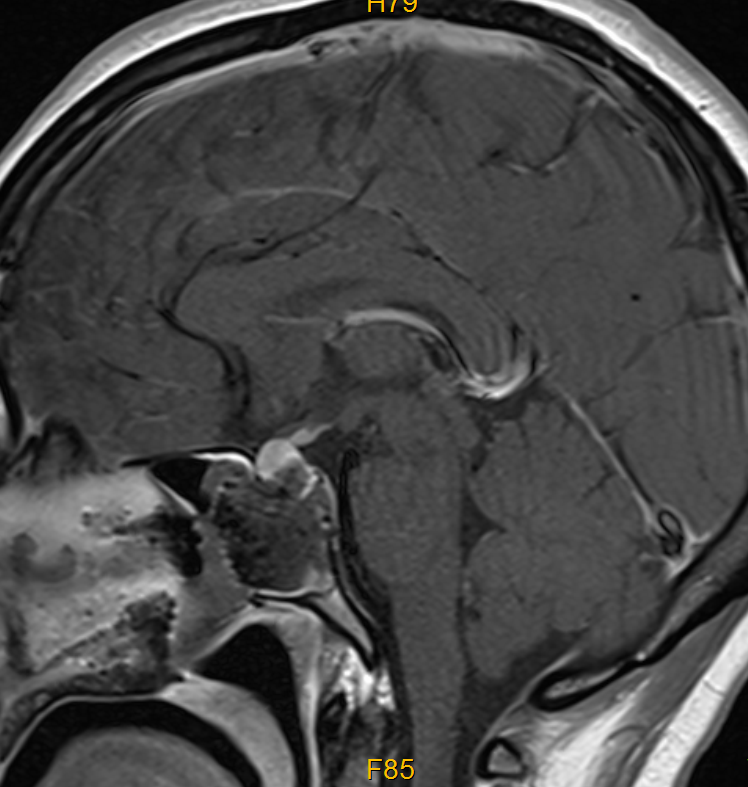

手术当天,医生在显微镜的高清视野下,通过一侧鼻孔逐步抵达垂体瘤位置,小心翼翼地清除了出血组织并完整切除肿瘤,整个过程未损伤周围的神经、血管,也没有打开颅骨。

由于手术创伤小,她术后恢复很快,没有出现并发症。后续病理检查确诊为垂体腺瘤,而术后复查显示,肿瘤及出血已彻底清除,头痛根源被完全解决。